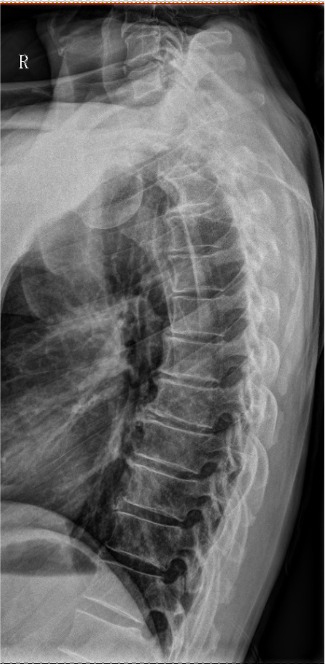

【影像】胸椎正侧位X线片见胸椎退行性变,胸椎轻度侧弯。